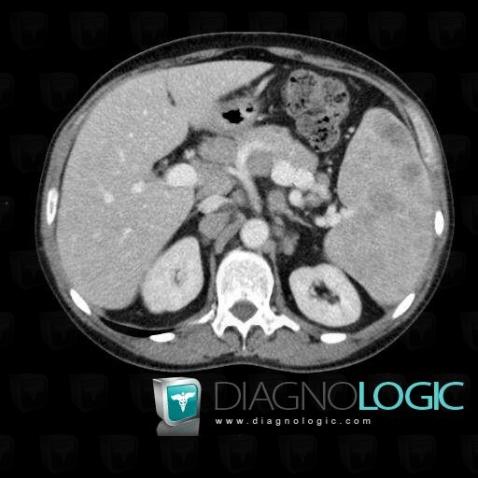

Lymphome , Rate, Scanner

Voici les informations spécifiques à l'image clé ci dessus:

- Diagnostic Lymphome , Localisation(s) Rate, comportant les gammes Splénomégalie, Lésion splénique solide, Lésions spléniques multiples, Lésion splénique hypodense / kystique